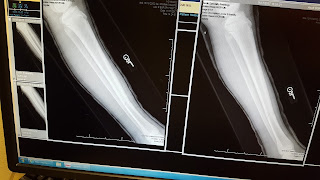

After Talmage had been in a cast for a week we went back to follow up with the Dr.  Things are pretty stable, but unfortunately the bone was starting to bow.  It was still in a normal range, but something to be sure didn't get worse.  Well, instead of just watching the progress for the next week they decided to re-cast his leg to try to correct the bow now.  After just having a cast for a week Talmage's leg was still really tender.  He was happy when they were finally done and his leg was stable again.  Poor guy, as if having a cast in the first place wasn't hard enough.

Before and after pictures of the bone bowing and the correcting.

Grant was there to help me get him into the urgent care.  I told them I think he broke his leg and they got us back and x-rayed.  The Dr. was thinking that I was probably overreacting, until he saw the x-ray.  It was definitely broken!  Poor guy.  They fitted him with a splint with instructions to get into an orthopedic doctor to get casted.

Friday we got him in and got new x-rays and a full leg cast.  The cast is supposed to last 6 to 8 weeks.  That makes for a long time without showers!  Talmage's pain was pretty strong on the first day, but the IBuprofen has kept it pretty controlled.  I'm glad he is surviving as well as he is!

The break.  Lateral view of his tibia

Close up frontal view

The new x-ray.  Poor leg!